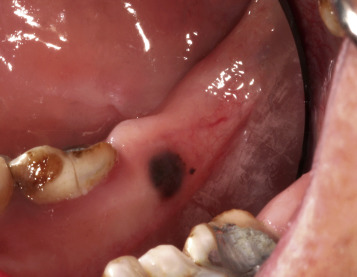

- •

Amalgam tattoo is characterized by painless, gray, bluish, black, or slate-colored macules that occur on the gingival/alveolar ridge or buccal mucosa.

Gray, bluish, black, or slate-colored macules can be seen on the gingival/alveolar ridge or buccal mucosa ( Fig. 3.16 ).

FIG. 3.16

Amalgam tattoo is a benign hyperpigmented area of the gingival mucosa adjacent to teeth with amalgam fillings.

(From Fitzpatrick J and Morelli J, Dermatology Secrets Plus , 5th Edition, Philadelphia, PA: Elsevier, 2016.)